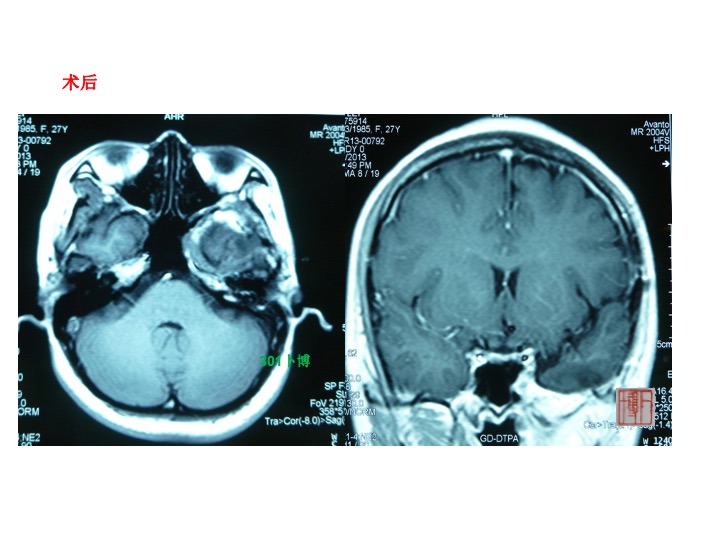

病例2,女性,26岁。主因头痛左侧面部麻木半年个月入院。查体:左侧面部痛温觉减退,左侧咀嚼肌肌轻度萎缩。MRI示左侧中颅窝底鞍旁颞下窝长T1长T2占位,可明显强化。大部分肿瘤位于颞下窝。术后强化MRI提示肿瘤切除理想,同时可见患者颞肌萎缩。